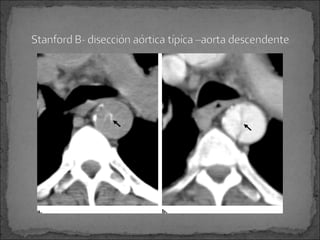

Stanford tipo B:

 Es tratada medicamente para HTA a menos que ocurra

alguna complicación -isquemia orgánica abdominal o

dolor persistente Cirugía

TC: ruptura y desplazamiento de la íntima.

Pueden hacer presentaciones típicas y atípicas que nos

puede dificultar el diagnóstico.